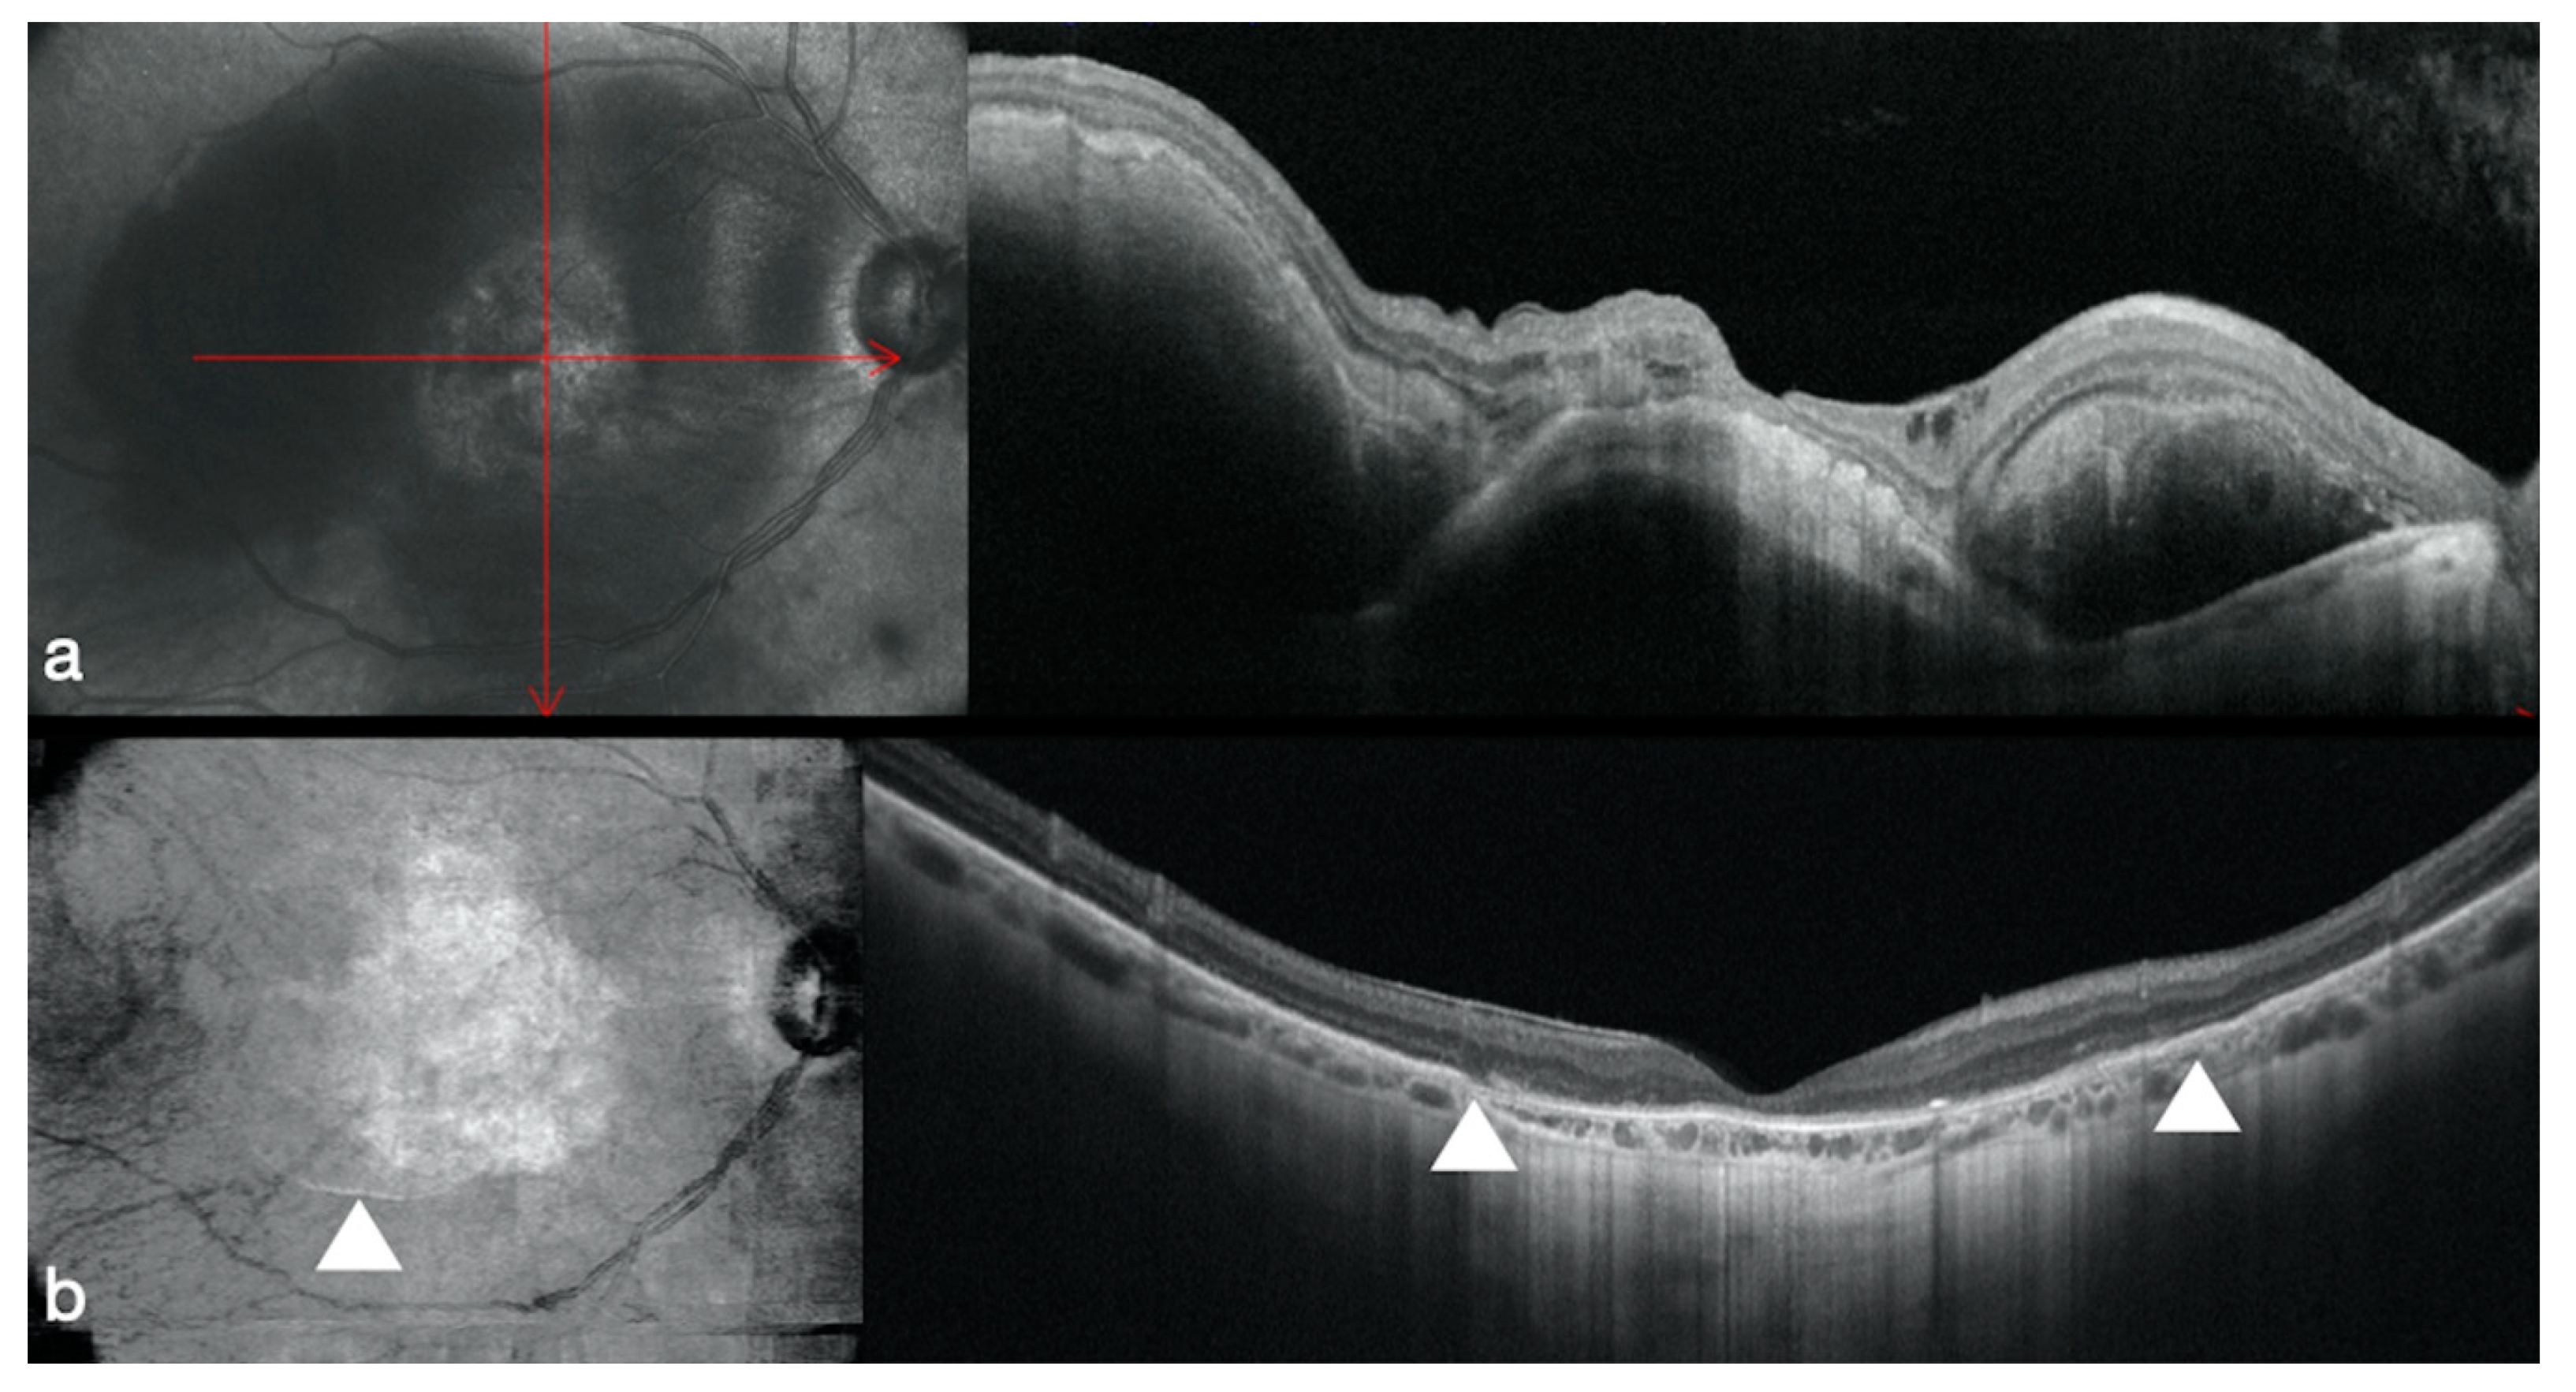

3.4. Optic Disk Pit Associated Macular Detachment

- Rizzo, S.; Caporossi, T.; Pacini, B.; De Angelis, L.; De Vitto, M.L.; Gainsanti, F. Management of Optic Disk Pit-associated Macular Detachment with Human Amniotic Membrane Patch. Retina 2020. [Google Scholar] [CrossRef] [PubMed]

- Postel, E.A.; Pulido, J.S.; McNamara, J.A.; Johnson, M.W. The etiology and treatment of macular detachment associated with optic nerve pits and related anomalies. Trans. Am. Ophthalmol. Soc. 1998, 96, 73–88; discussion 88–93. [Google Scholar]

- Garcia-Arumi, J.; Guraya, B.C.; Espax, A.B.; Castillo, V.M.; Ramsay, L.S.; Motta, R.M. Optical coherence tomography in optic pit maculopathy managed with vitrectomy-laser-gas. Graefes. Arch. Clin. Exp. Ophthalmol. 2004, 242, 819–826. [Google Scholar] [CrossRef]

- Hirakata, A.; Okada, A.A.; Hida, T. Long-term results of vitrectomy without laser treatment for macular detachment associated with an optic disc pit. Ophthalmology 2005, 112, 1430–1435. [Google Scholar] [CrossRef]